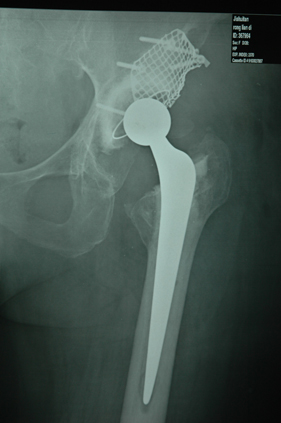

rivision total hip replacement for dislocation and severe bone defect

(post-op)rivision total hip replacement for dislocation and severe bone defect

anterior-posterior view of left hip

lateral view of left hip